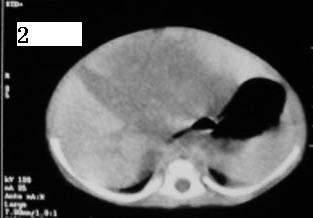

这个病例定位诊断:1、可以肯定肿块不在肝脏。2、肿块在腹膜后,因为肠管向前侧方推移,肾脏明显向后推挤,腹主动脉及下腔静脉被肿块包绕。

定性诊断比较困难,该病例肿块为实质性,小儿最常见的腹膜后肿瘤第一位应该是-----神经母细胞瘤!

我的意见是-----定位诊断是“1、可以肯定肿块不在肝脏。2、肿块在腹膜后,因为肠管向前侧方推移,肾脏明显向后推挤,腹主动脉及下腔静脉被肿块包绕。”

肝脏只是受推压改变,支持神经母细胞瘤

右中下腹部囊实性密度影,内有小细条状钙化影,胃及腹部肠管受压向左移位,肾脏受压向后移位,腹主动脉及下腔静脉包饶。考虑腹膜后畸胎瘤可能性大。